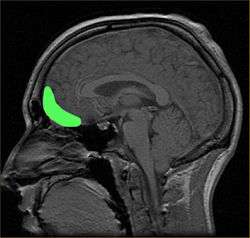

![]() Approximate location of the OFC shown on a sagittal MRI | |

The orbitofrontal cortex (OFC) is a prefrontal cortex region in the frontal lobes in the brain which is involved in the cognitive processing of decision-making. In non-human primates it consists of the association cortex areas Brodmann area 11, 12 and 13; in humans it consists of Brodmann area 10, 11 and 47[1]

The OFC is considered anatomically synonymous with the ventromedial prefrontal cortex.[2] Therefore, the region is distinguished due to the distinct neural connections and the distinct functions it performs.[3] It is defined as the part of the prefrontal cortex that receives projections from the magnocellular, medial nucleus of the mediodorsal thalamus, and is thought to represent emotion and reward in decision making.[4] It gets its name from its position immediately above the orbits in which the eyes are located. Considerable individual variability has been found in the OFC of both humans and non-human primates. A related area is found in rodents.[5]